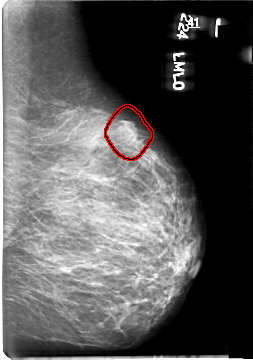

D_4061_1.LEFT_MLO

LEFT_MLO LINES 5386 PIXELS_PER_LINE 3781 BITS_PER_PIXEL 12 RESOLUTION 43.5 OVERLAY

FILE: D_4061_1.LEFT_MLO.OVERLAY

TOTAL_ABNORMALITIES 1

ABNORMALITY 1

LESION_TYPE MASS SHAPE ROUND MARGINS OBSCURED

ASSESSMENT 0

SUBTLETY 4

PATHOLOGY BENIGN

TOTAL_OUTLINES 1

BOUNDARY